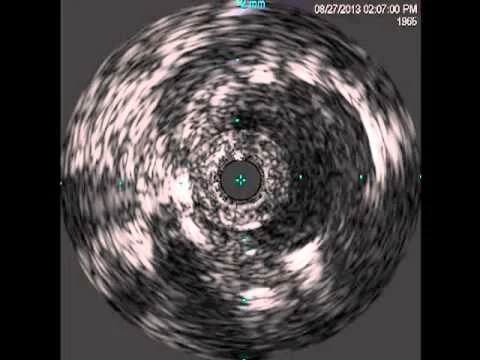

Infrared-X IVUS Before and After SFA Intervention